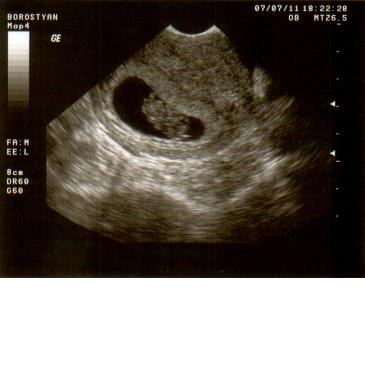

Szóval a szerda története, amikor kiderült, hogy két babánk lesz egyszerre:

Tegnapelőtt kellett visszamennem a dokihoz, aki hétfőn szabadságra megy 3 hétre. Rávettem a páromat, hogy kisérjen el, és örülök, hogy eljött velem, mert egyedül nem biztos, hogy hazataláltam volna! Szerdán tehát visszamentem kontrollra, ahol nagyon jól elbeszélgettünk az orvossal, megkérdezte, hogy hogyan érzem magam, van-e panaszom. (Szegény párom szerintem már itt rágta a körmét a váróban, mert a többiek előttem max. 5 percig voltak bent!) Mikor befejeztük a helyzetelemzést elkezdte a vizsgálatot. Közölte, hogy a méhszáj zárt, nagyon jó! Következett az UH-os vizsgálat. Már az elején sejtettem, hogy valami van, mert néha elég érdekes lett a feje! Hosszas vizsgálódás után megkérdezte az orvos, hogy mit szólnék ha azt mondaná, hogy ketten vannak?! Teljesen lefagytam! Mondtam neki, hogy két gyereket szerettünk volna, de nem egyszerre! Azóta sem tudom felfogni a dolgot, egyenlőre ott tartunk, hogy a párommal győzködjük egymást a UH felvételt nézegetve, hogy megtörtént velünk is a csoda, ikreink lesznek! (Remélem, minden rendben lesz velük, nem fog kiderülni semmi negatív dolog, mert kezdem magam teljesen beleélni a dupla baba gondolatába! :oops: :roll: )

Kép 9 hetesen az egyik Kép 9 hetesen a másik

rnecsi

Kép Mégegyszer az első :)

Sajnálom lányok! Az egyik nagyon szégyelős! Lehet, hogy kislány? :lol:

Sikerült előcsalogatni! :D

Kép